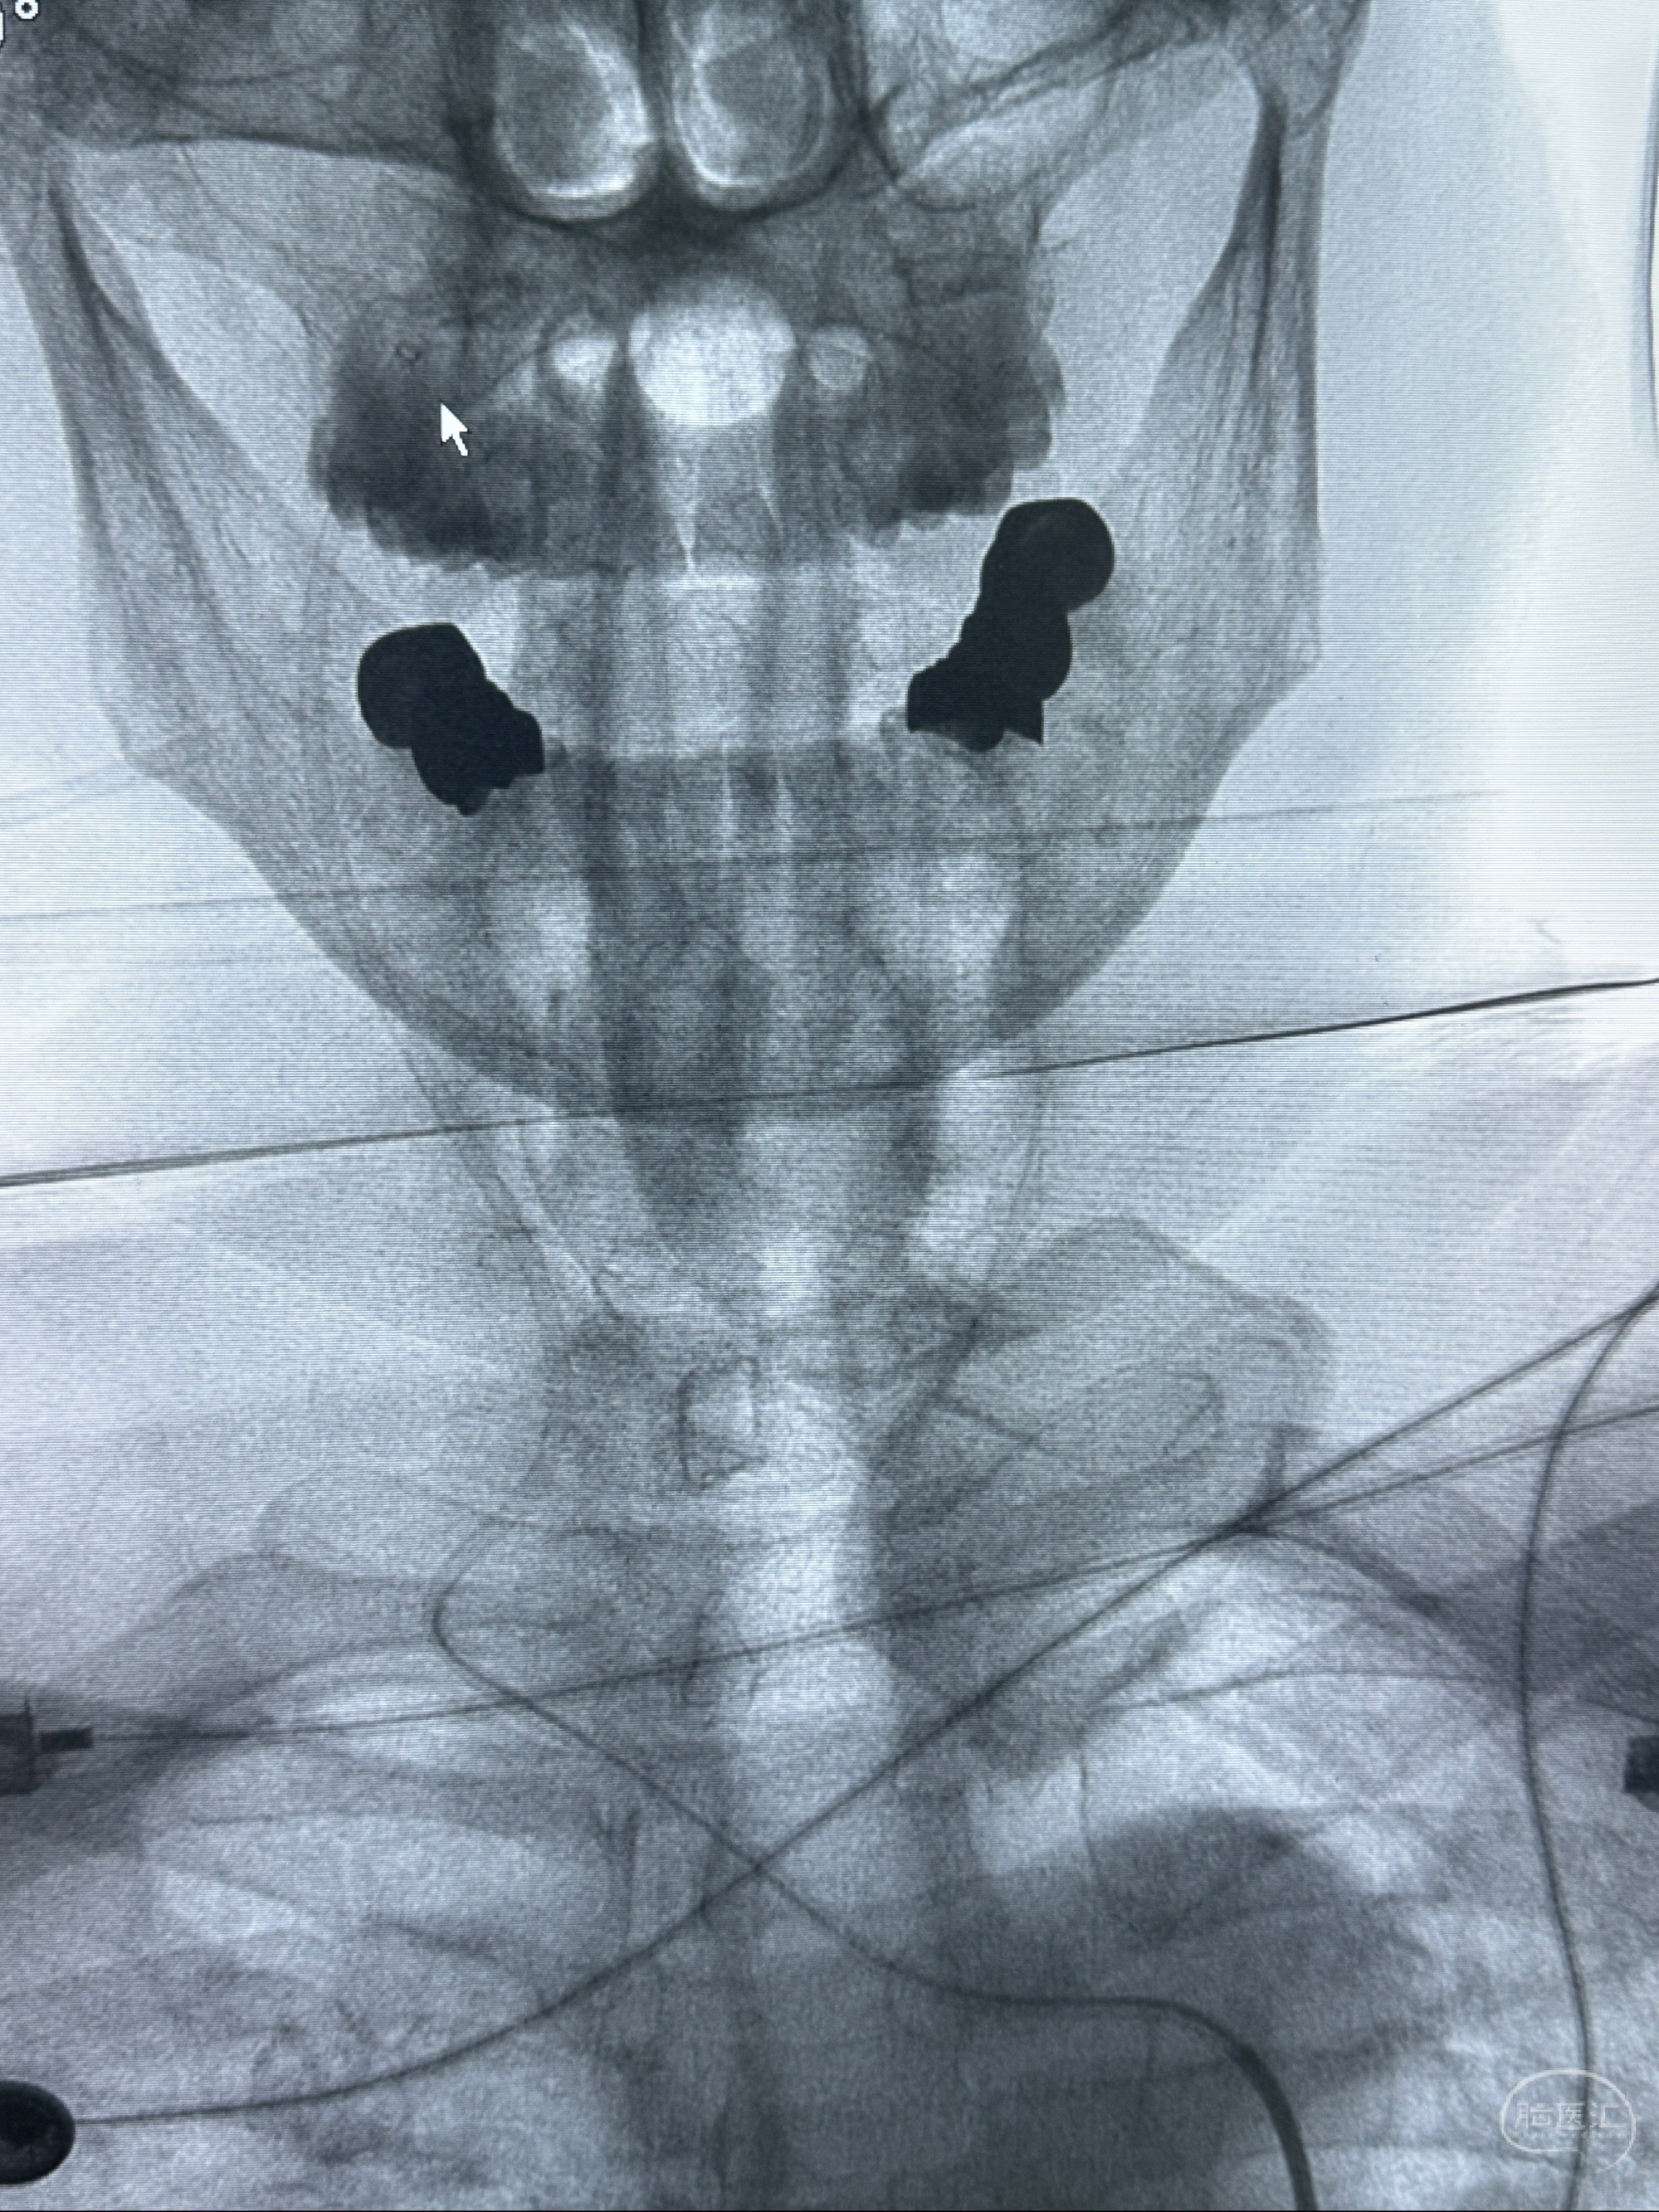

2023-12-04全麻下行支架辅助治疗

S-AB4-20mm

麻醉苏醒佳,遵嘱动作